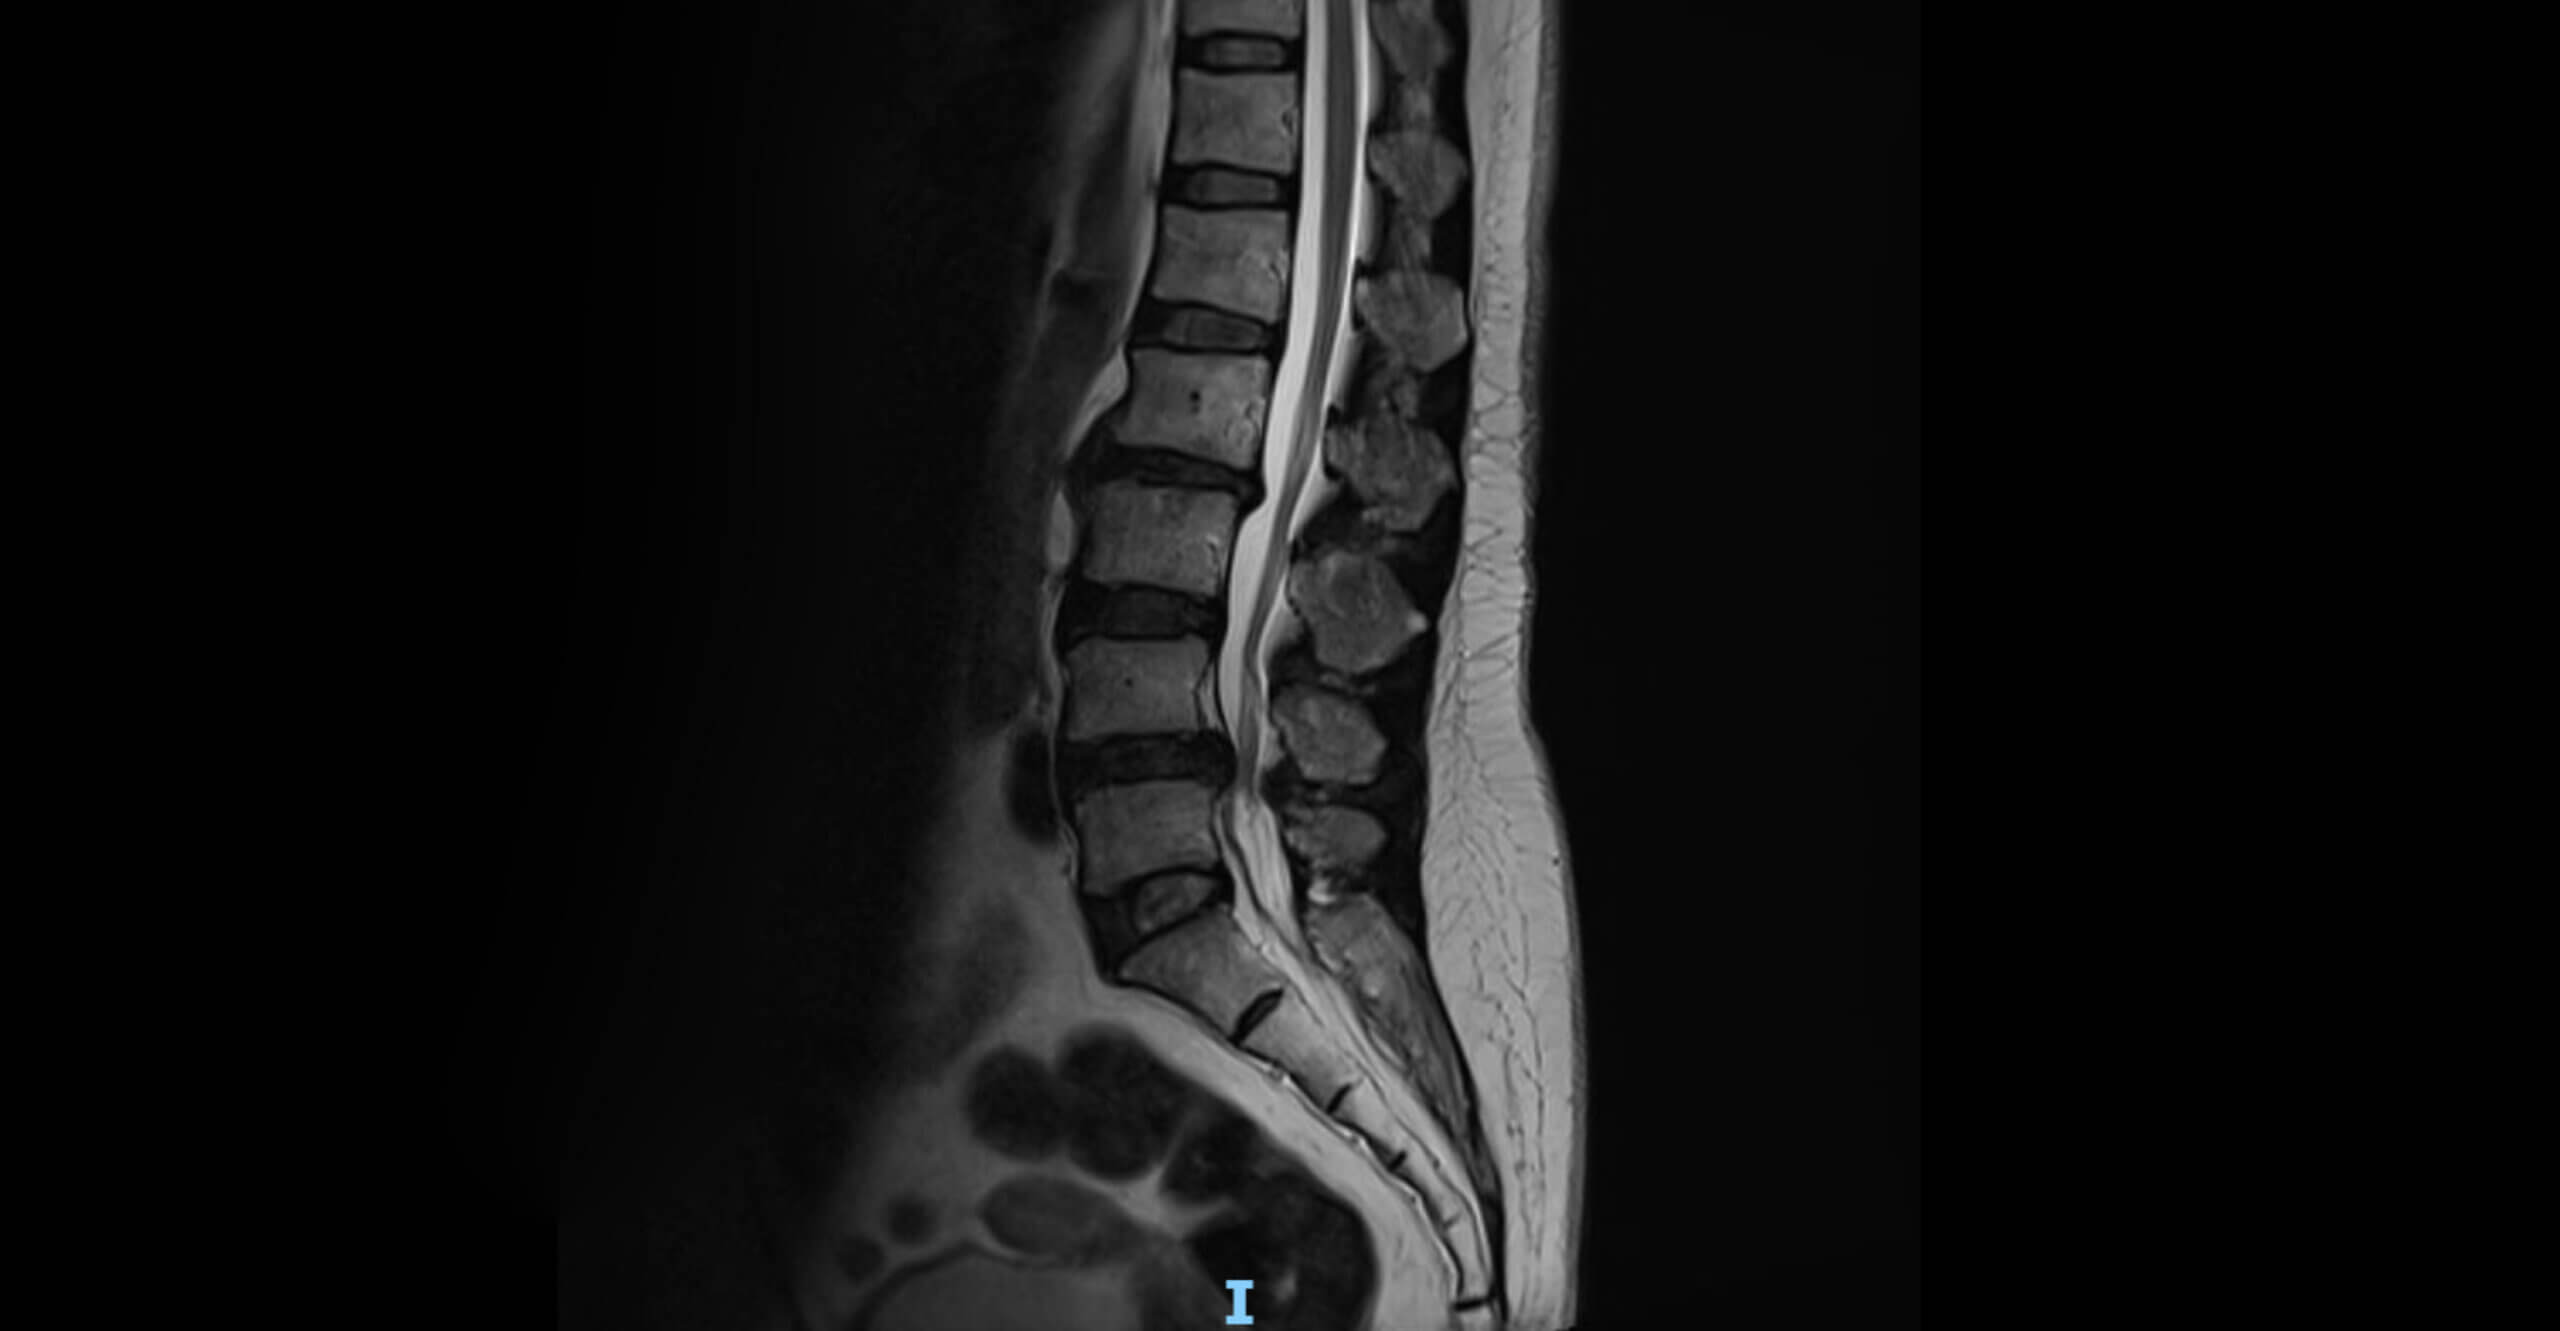

An MRI (Magnetic Resonance Imaging) provides detailed images of:

• Herniated discs

• Bulging discs

• Degenerative disc disease

• Nerve compression

• Spinal stenosis

• Disc dehydration

• Annular tears

This information allows doctors to determine whether spinal decompression is the correct treatment option.